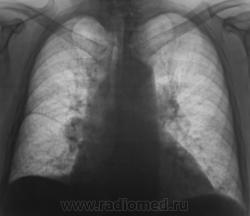

При расшифровке флюорограмм пациент "взят на контроль". Произведено стандартное дообследование.

Ваше мнение коллеги?

Эта штучка неотделима от правой промежуточной артерии...

А что там в легких: фиброз, склероз, диссеминация? Почему этого не видно на томо?

На "томо" шикарно видно:

1. Гиповентиляцию правого лёгкого.